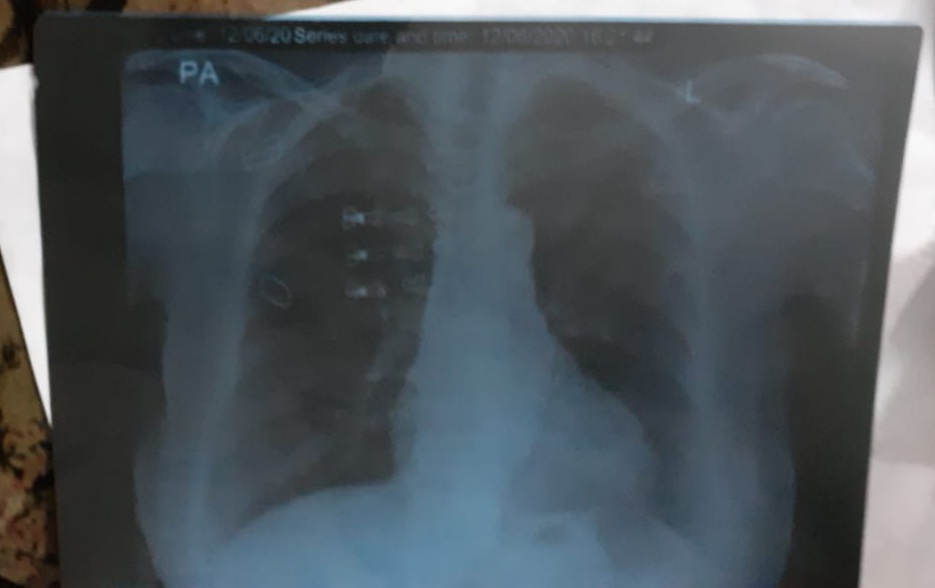

Salam My mother 68 years old having history of asthma and hypertension. From 4th June she started having mild fever &sore subsided after 3 days but there was loss of appetite and dry cough but little xray and cbc gave antibiotics but she started having vomiting thn we finally went to her pulmonologist and he asked for has now examined her personally and prescribed is little better question is the disease on initial stage or some recovery phase has started? or something to worry about ? attaching all reports

nothing to worry now